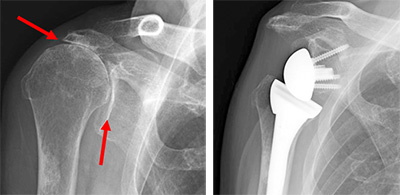

軟骨がすり減った事により骨同士が擦れ合う事で痛みを生じる疾患です。

まずは保存療法の適応となりますが、保存療法に反応しない場合が多いのも事実です。

保存療法に抵抗性の場合は患者様の生活レベル、年齢なども考慮し、希望があれば手術療法をお勧めさせていただいております。その際は希望に応じて大阪ショルダーチームでも特に人工関節を専門としている病院(年100例以上)へご紹介させていただきます。最近では従来の人工関節に加えてリバース型人工関節も行えるようになり、安定した治療成績を得る事が出来ております。